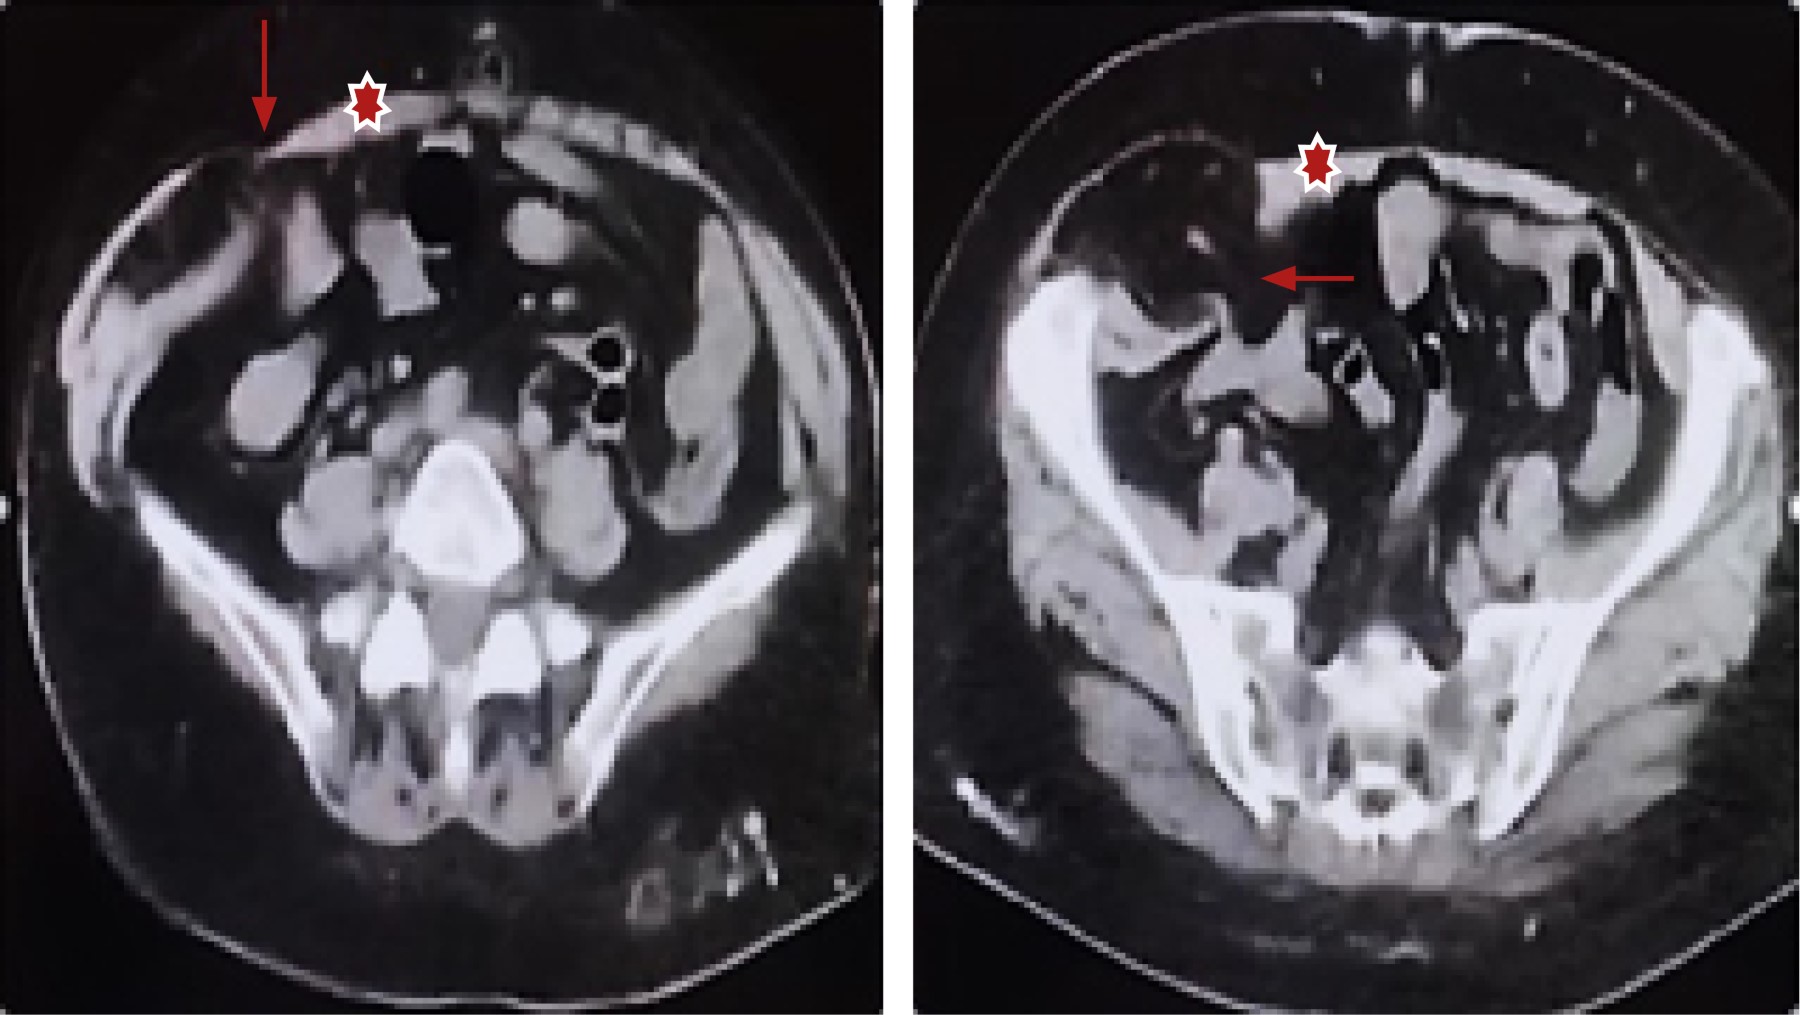

Para tener los mejores resultados posibles en la realización de la cirugía, siempre es útil un periodo de prehabilitación de cuatro semanas, además preferimos evaluar algunos aspectos antes del procedimiento de acuerdo con las guías STRONG del American College of Surgeons,7 atendiendo cuatro áreas: Nutrición, tabaquismo, glucemia y manejo de medicamentos. Para la cirugía electiva es importante asegurarse de que los pacientes dejen de fumar y que su índice de masa corporal sea el menor posible. Para confirmar el diagnóstico, se realiza una exploración física de la pared abdominal y en todos los casos se solicita una TC abdominal (Figura 1).

Figura 1